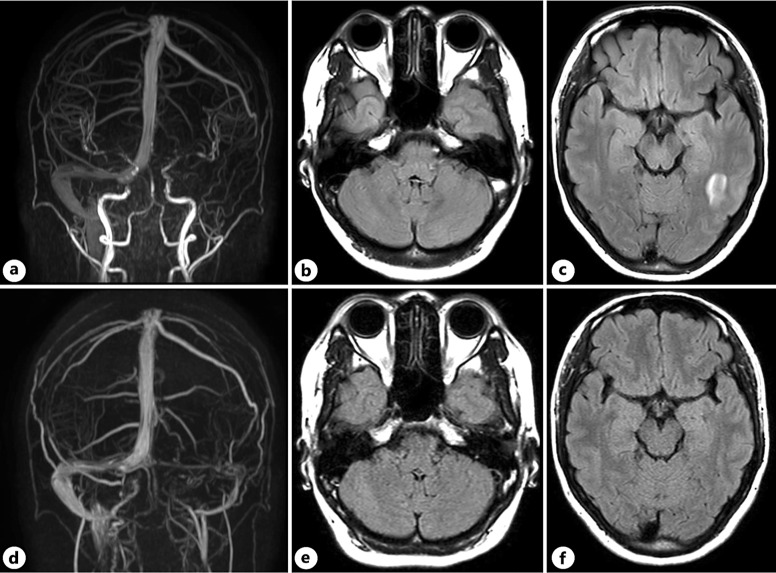

Case presentation: A 29-year-old Nepalese woman developed DVT during her first pregnancy. Examination revealed no thrombophilic predisposition. The thrombus resolved with oral anticoagulant medication, which was discontinued after 3 months. During the second pregnancy, prophylactic subcutaneous heparin injections were initiated to prevent venous embolism. Following several days of non-administration of heparin, she experienced left occipital pain, and magnetic resonance venogram showed left CVST. Oral anticoagulants were initiated, and her headache resolved within a few days. Additional blood tests showed abnormally high levels of Lp (a) at 113 mg/dL. Six months later, the CVST was partially recanalized.